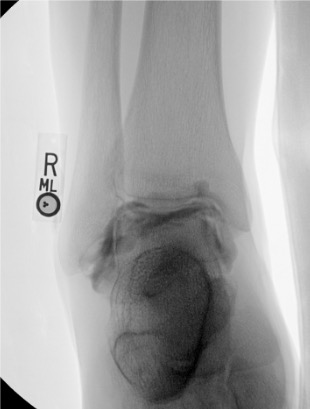

Elbow

Posterior (olecranon fossa)

Olecranon fossa with elbow flexed 90°; needle directed anteriorly into trochlear notch

8–10 mL